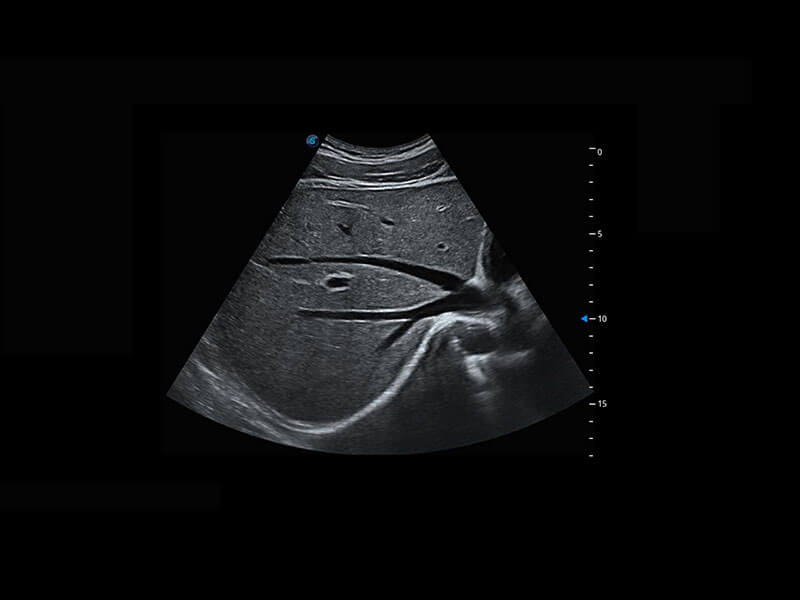

• 四腔切面

• 四腔心血流